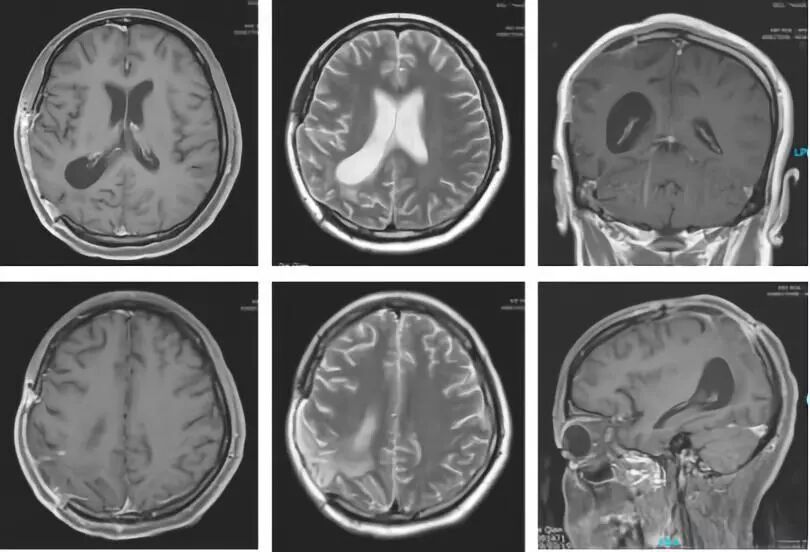

2017年6月4日,对患者保肝治疗两天后进入天坛医院血液肿瘤科进行维莫非尼治疗,用药6天半皮疹严重,停药5天后继续用药,用药一个周期后,复查(图10)MRI示病情得以控制,继续6个周期替莫唑胺辅助化疗(图11),持续动态观察(图12,13,14),直至最近于2018年12月08日于湘雅医院复查(图15),病情无进展,患者神清,自主活动,一般情况良好,母子生活质量理想。

图10. 维莫非尼治疗一个周期后复查MRI

图12. 维莫非尼治疗后复查(2017.12.14)

图13. 维莫非尼治疗后复查(2018.03.20)

图14. 维莫非尼治疗后复查(2018.06.09)

图15. 最近复查结果(2018.12.08)